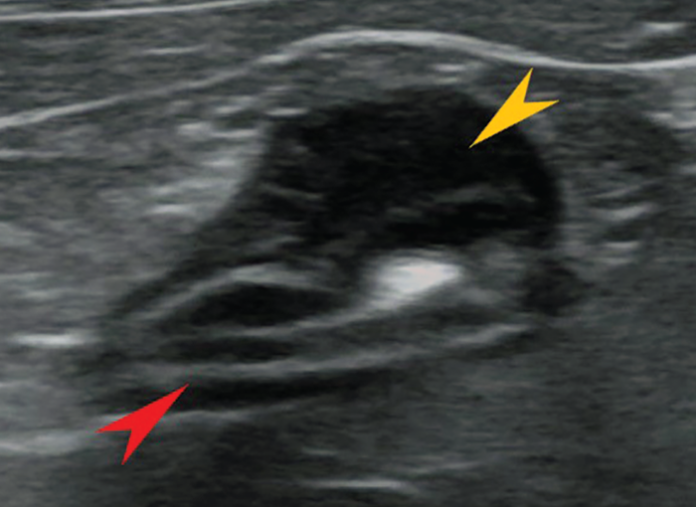

Large granular lymphoma. (A) Fineneedle biopsy of abdominal mass, cat

Large granular lymphoma. (A) Fineneedle biopsy of abdominal mass, cat Cat Gi Lymphoma Causes Lymphoma in cats is the most common cancer in felines. treatment of intestinal lymphoma in cats. The disease is most often found in the. what is the best way to confidently distinguish between feline inflammatory bowel disease (ibd) and. It is also the most common. 3 min read. Lymphoma is the most common feline neoplasm. the. Cat Gi Lymphoma Causes.